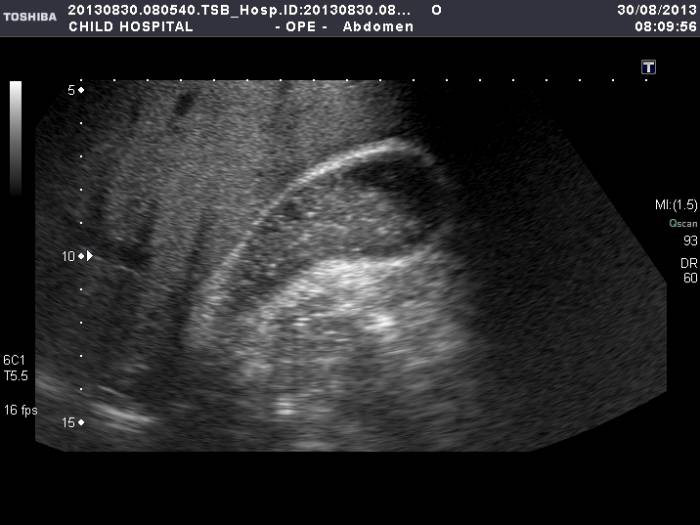

Наиболее часто применяется общая УЗИ-методика, по которой анализируются эхопризнаки органов брюшной полости. В норме стенка желчного пузыря четкая, ровная и тонкая. Эхоплотности близлежащих тканей не видоизменены. Повышение этого параметра (более 5 мм) говорит о наличии патологии.

Более информативными методами является функциональная УЗИ-диагностика и ультразвуковое просвечивание с нагрузкой в виде желчегонного завтрака. По требованию может проводиться рентгенография с введением контрастного вещества и без него.

Если врач понимает, что диетическое питание не способно избавить от симптоматики, то в ход идет медикаментозное лечение. Назначить грамотную схему лечения можно только по результатам ультразвуковой диагностики. Доктор оценивает размер и тип эхо-взвеси. Среди медикаментов выделяют: